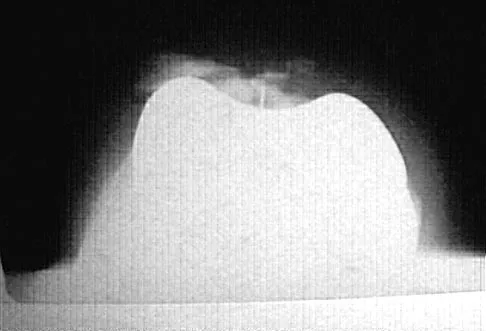

An 11-year-old boy has had a fever and pain and swelling over the lateral aspect of his right ankle for the past 3 days. Examination reveals warmth, swelling, and tenderness over the lateral malleolus, and he has a temperature of 103.2 degrees F (39.5 degrees C). Laboratory studies show a WBC count of 13,200/mm3 with 61% neutrophils, an erythocyte sedimentation rate of 112 mm/h, and a C-reactive protein of 15.7. Radiographs and a T2-weighted MRI scan are shown in Figures 13a through 13c. Aspiration yields 1 mL of purulent fluid. Management should now consist of

Explanation